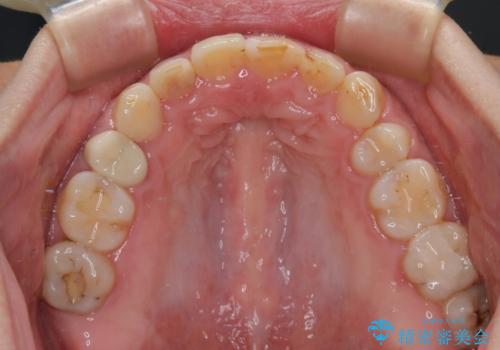

- 前歯のデコボコと前方に斜めに飛び出した前歯を気にして来院された患者様です。

口元の突出感はあまり気になっていませんでしたが、上下の前歯の前後差が大きかったため、上顎左右の第一小臼歯を抜歯し、上顎が裏側装置であるハーフリンガルにて矯正治療を行うこととしました。

矯正治療後は、気になっていた銀歯を全てセラミックとし、きれいな口元に仕上げることができました。